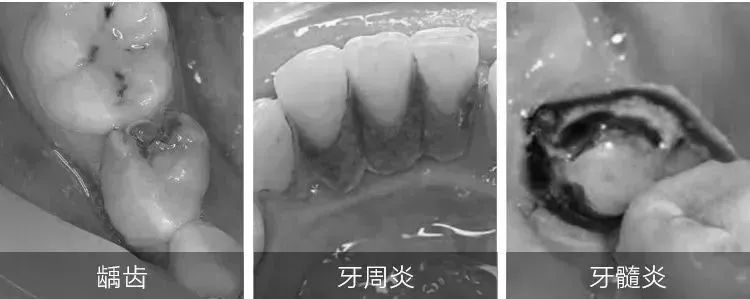

一开始是齿面有黑斑,没过多久黑斑变成了裂缝,随之而来的龋齿(牙洞、蛀牙),遇到酸的、冷的、甜的,敏感疼得要命。

俗话说“牙疼不是病,疼起来要人命”,其实牙疼本身就是一种病,一旦发生了牙疼,就说明牙上出现了龋洞,造成牙本质外露,会有剧烈疼痛感!

而且,据世卫组织统计,有龋齿牙洞、牙黑斑的人,口腔问题是普通人的10倍以上:常伴有牙结石、牙菌斑、黄牙,普遍嘴巴有浓烈的口臭,牙龈红肿出血、萎缩。

一旦牙釉质受损,就会出现牙齿敏感、发黄、黄斑、杂色、蛀牙、牙裂纹等问题。